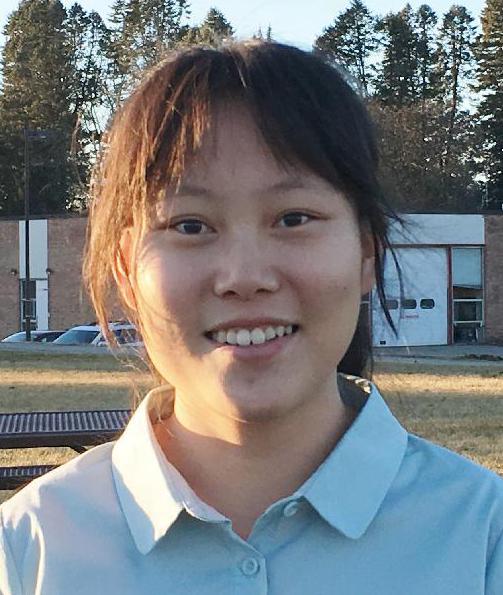

Student Spotlight: Mai Le – Finding a better way to diagnose breast cancer with MRI

The research group is using statistical signal processing to create crisper images with only 20% of the data required by a traditional MRI scan.

Mai Le receives CoE Distinguished Leadership Award

Mai has served as Community Service Co-chair of the Graduate Society of Women Engineers since arriving at Michigan in 2011.